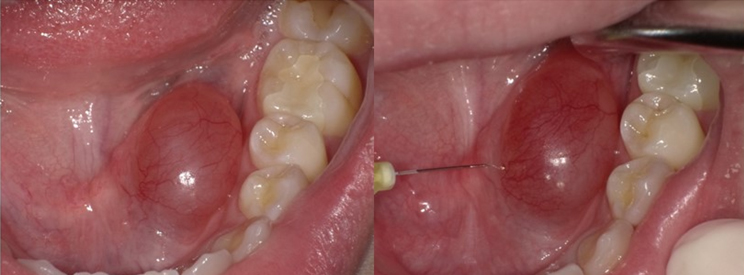

OK-432の注入療法

高濃度注入法27-30Gの注射針で嚢胞へ直接注入する方法。